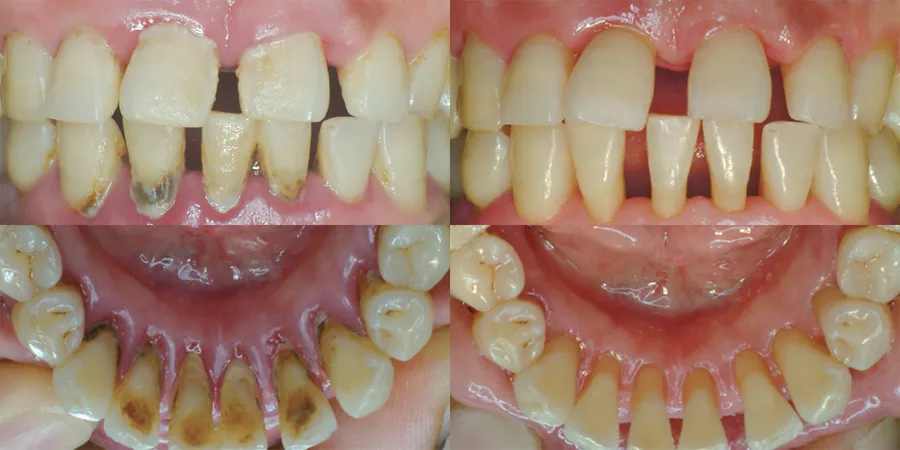

上の写真のように、スケーリングは目で見える「歯肉縁上」部分に付着した歯石や歯垢を除去する治療方法です。

一方、ルートプレーニングは、上の写真のように「歯周掻爬術」または「歯肉縁下掻爬術」とも呼ばれ、目に見えない歯と歯茎の境界面「歯肉溝」にたまった歯石を除去する方法です。歯根面を滑らかにし、再付着を促進することを目的としています。

歯石は歯ブラシが届きにくい歯と歯茎の間、そして歯茎の深い部分の歯の根元に多くたまります。また、歯茎を損傷させる主な原因は、目に見える歯石ではなく、歯茎の深い部分に隠れている歯石です。